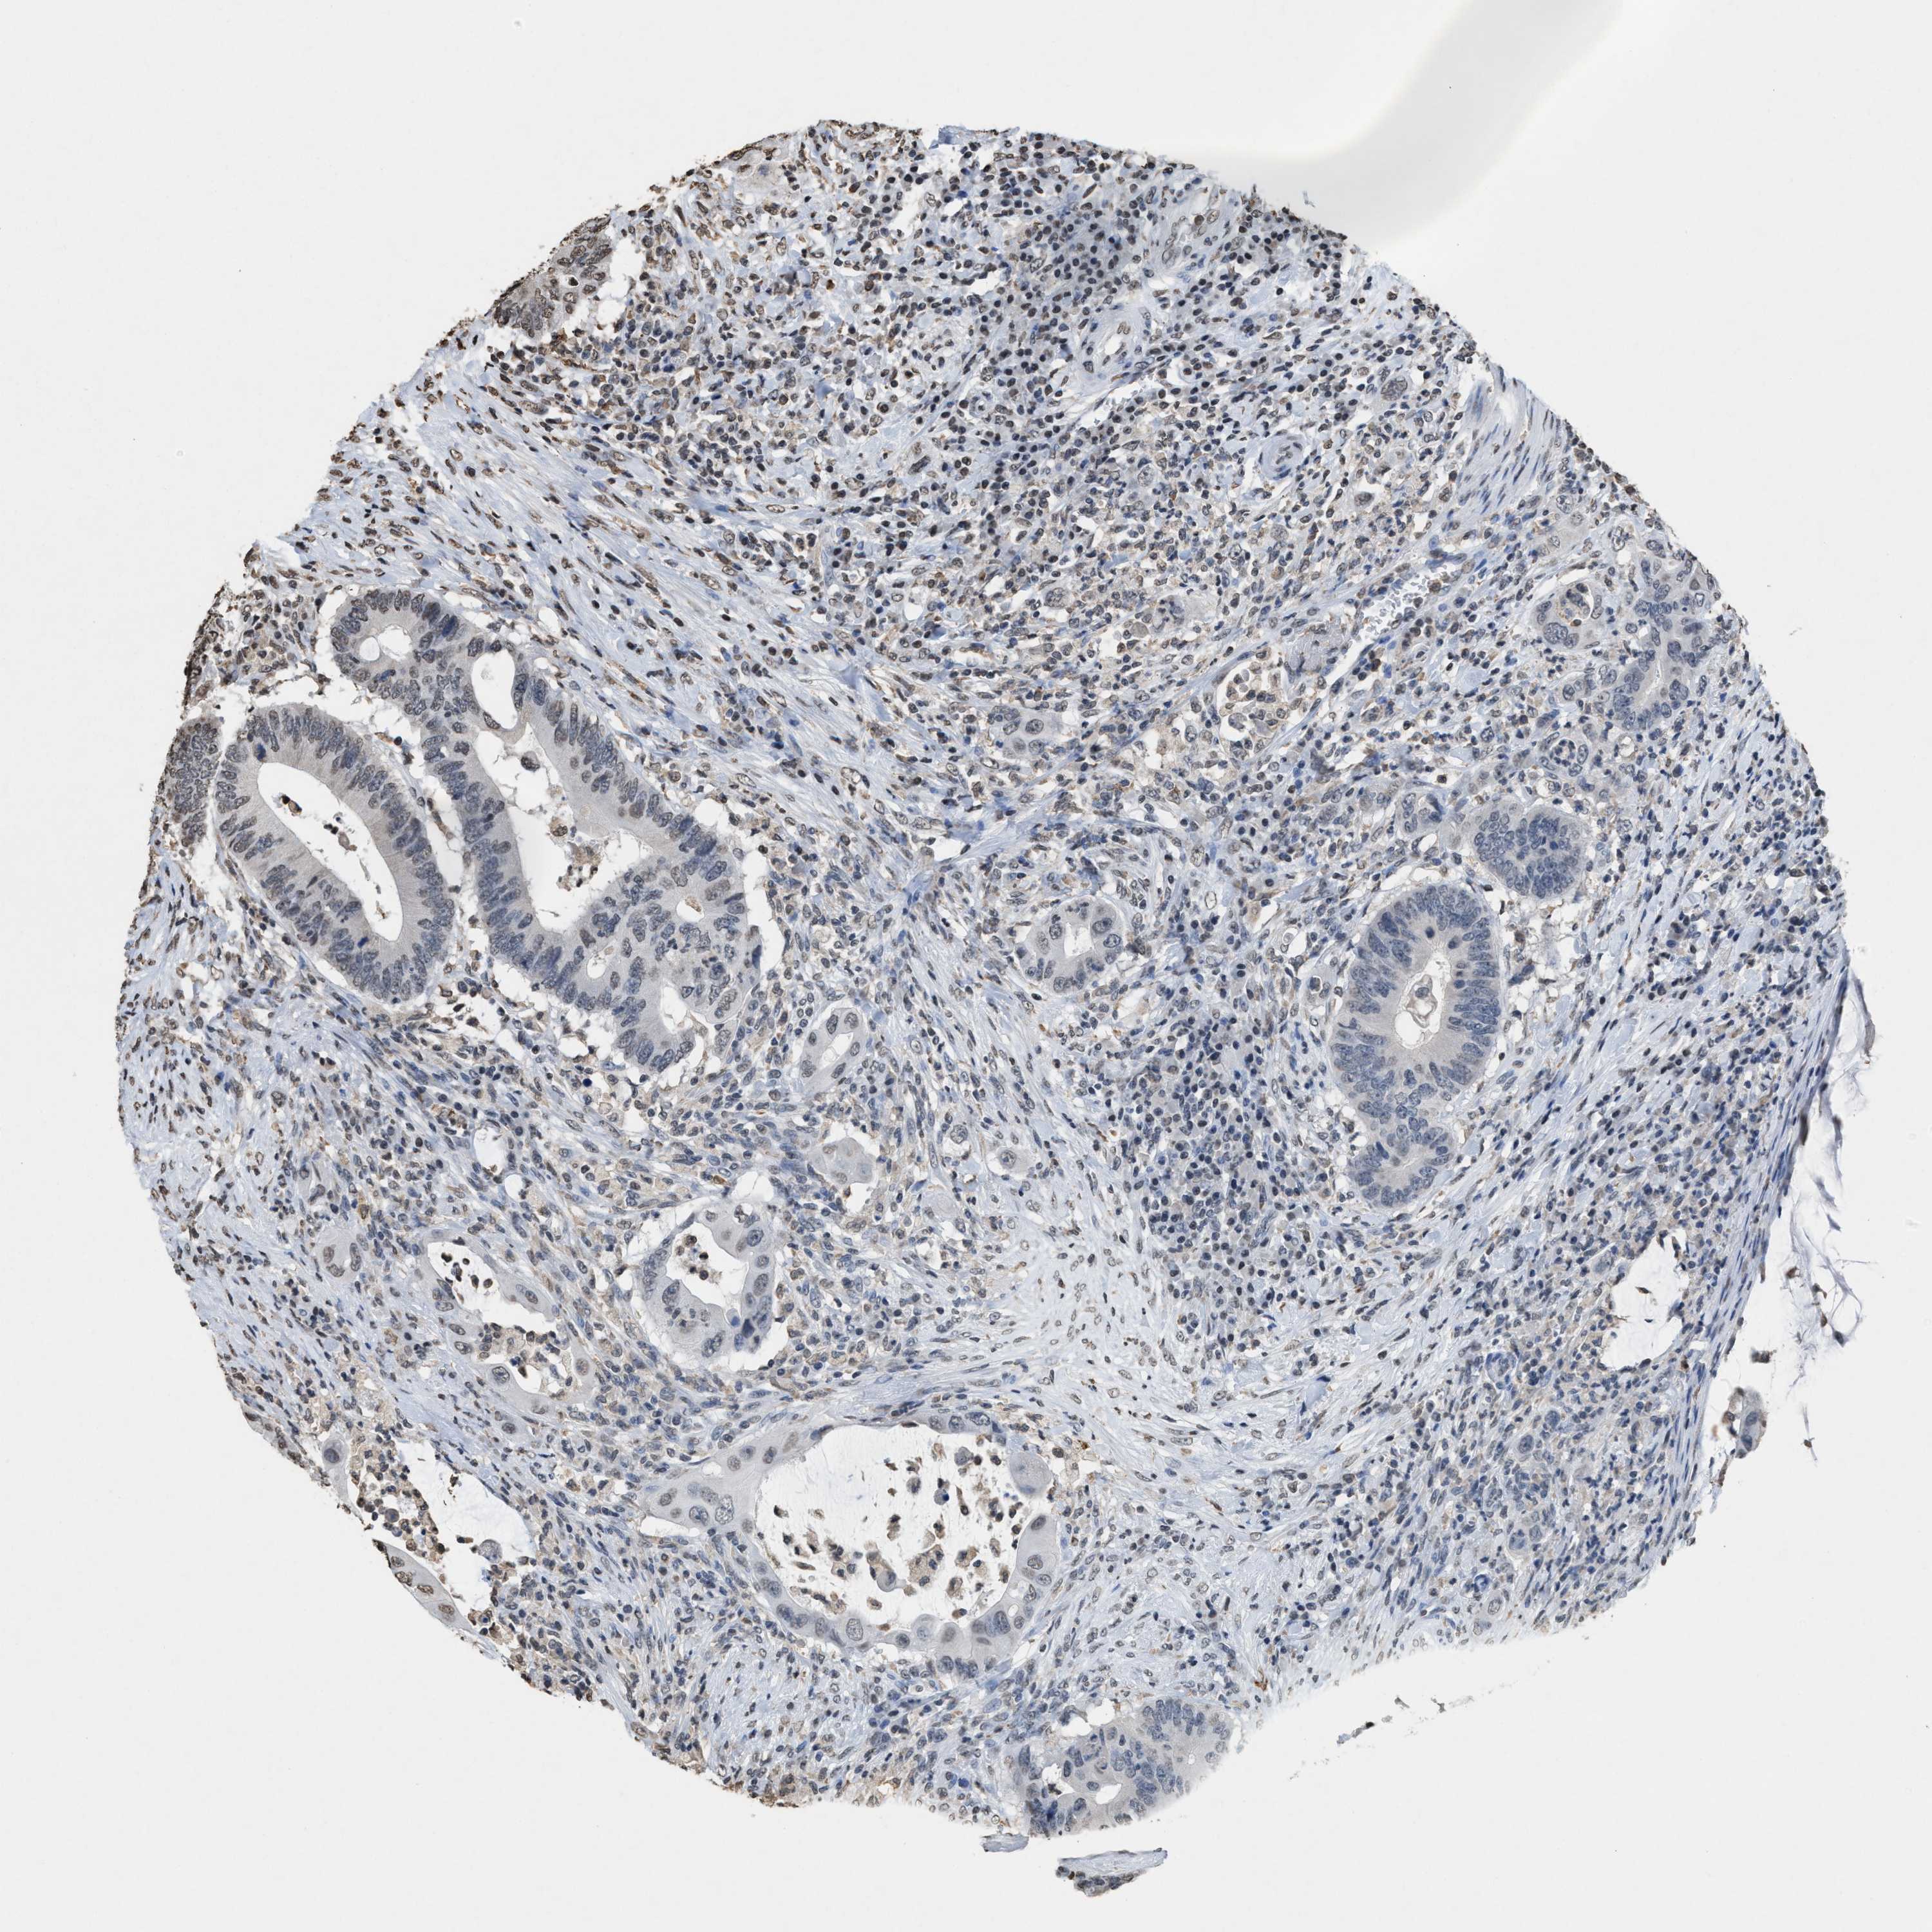

CANCER COLORECTAL CANCER Show tissue menu

Colorectal cancer

Human cancer

Colon adenocarcinoma